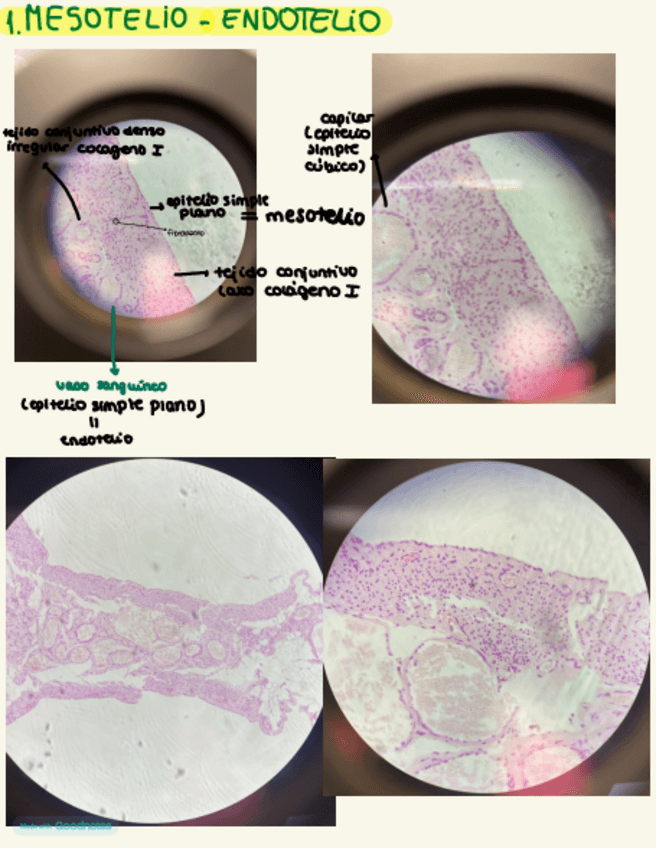

He publicado nuevos practicas de 1º Histología General: Practicas-Histologia-1.pdf

89 páginas